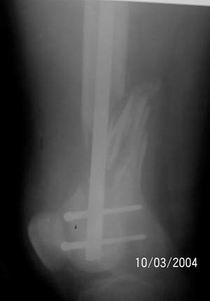

The femur injury was treated by long retrograde interlocking nail.

It seems you`d better to remove the nail and fix the

bone fragmenrs with DCS plate.

It was used ORTHFIX Retrograde nailing System, diameter 11.